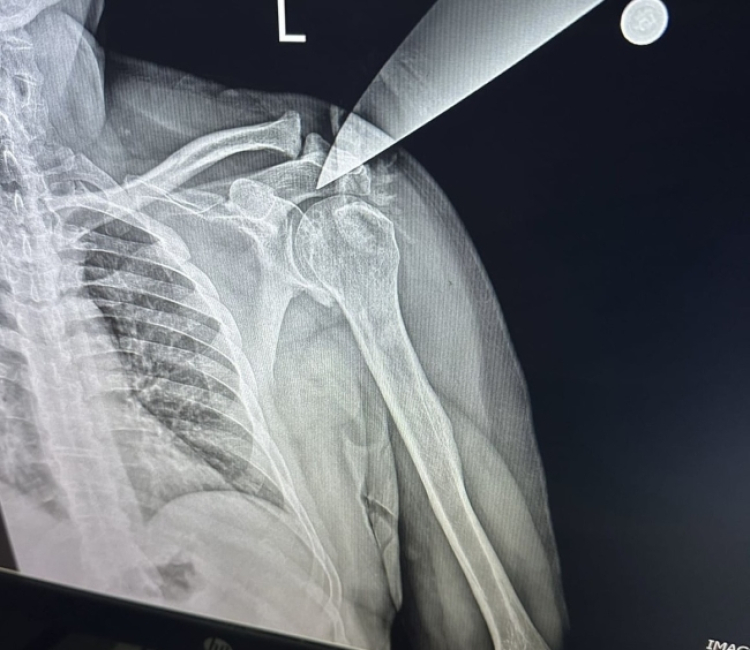

Korku dolu anlar yaşayan doktor ve klinikteki meslektaşları, 112 ekiplerini aradı. İhbar üzerine olay yerine gelen sağlık ekipleri, yaralı doktoru Yüksek İhtisas Eğitim ve Araştırma Hastanesine sevk ederken, doktorun omzuna saplanan bıçak ameliyatla alındı.